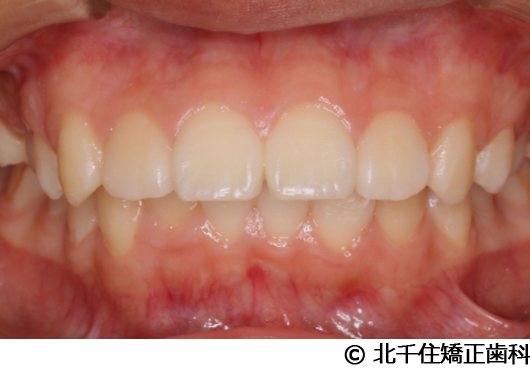

【症例5】上顎前突

- 治療前

- 治療後

- 治療名

- 上顎前突

- 費用

- 1,263,600円(税込)

- 期間

- 2年8ヵ月

- 治療回数

- 32回

- 通院頻度

- 1ヵ月ごと

- 年齢

- 13歳3ヵ月(初診時)

治療内容

-

患者様の症状

主訴:出っ歯

治療方法

骨格性の上顎前突、ヘッドギアを併用して上下顎第一小臼歯4本抜歯してワイヤー矯正。

治療結果

骨格性上顎前突に対し、ヘッドギアおよび抜歯を併用した矯正治療により歯列および咬合関係の調整を行った症例である。

治療後は保定装置を使用し、歯列および咬合の安定維持を目的として定期的な経過観察を行っている。

※治療結果は個人差があります。

治療を行う上での注意点(リスク・副作用)

歯磨き不良に伴うカリエスや歯周病、歯根吸収など。